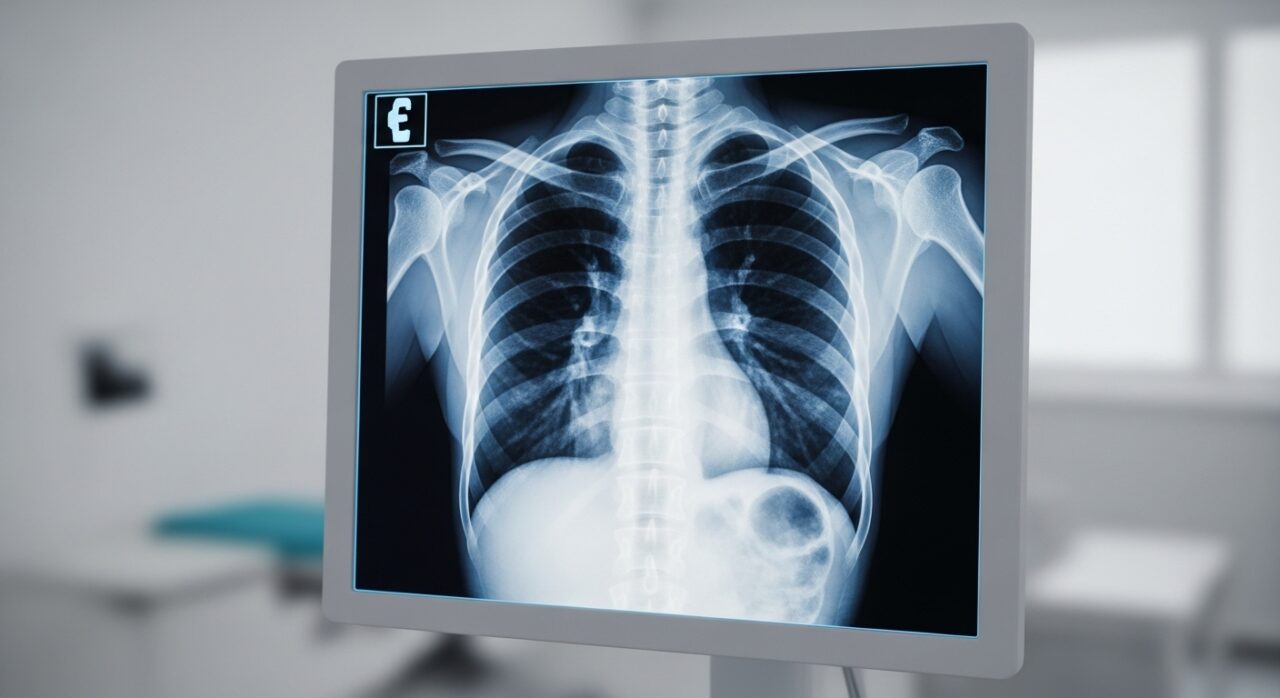

アスベスト(石綿)への暴露によって引き起こされる健康被害は、主に呼吸器系、中でも肺や胸膜に発生します。

肺がんも、アスベスト(石綿)暴露によって発生リスクが高まることが医学的に証明されている健康被害です。アスベストによる肺がんは、特に喫煙者がアスベストに暴露した場合に、相乗効果でリスクが飛躍的に高まることが特徴です。一般的な肺がんとアスベストによる肺がんを症状だけで区別することは難しいですが、アスベストが原因である場合は、病理検査によって肺組織内にアスベスト繊維(石綿小体)が確認されることがあります。アスベスト暴露歴がある方が、持続的な咳や血痰、胸痛などの症状を自覚した際には、必ず医師にその旨を伝える必要があります。

アスベスト(石綿)は、中皮腫や肺がん以外にも、いくつかの深刻な健康被害を引き起こします。石綿肺(じん肺の一種)は、多量のアスベスト繊維を吸入したことによって肺組織が硬くなる(線維化)病気です。初期は無症状ですが、進行すると呼吸機能が低下し、重度の呼吸困難を引き起こします。また、胸膜が厚く硬くなるびまん性胸膜肥厚や、胸水が溜まる良性アスベスト胸水などの胸膜疾患も、アスベスト暴露の代表的な健康被害です。これらの病気は、特に症状が慢性化しやすく、日常生活におけるQOL(生活の質)を大きく低下させます。診断は、CTスキャンなどの画像検査や呼吸機能検査に基づいて行われます。